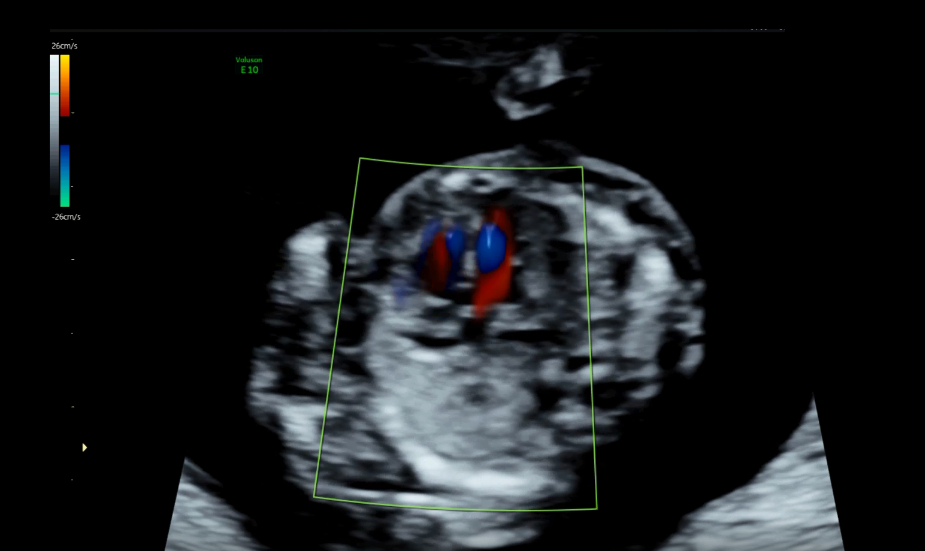

早孕期胎儿法洛四联症超声诊断学特征并文献复习

栾泽东

中华诊断学电子杂志